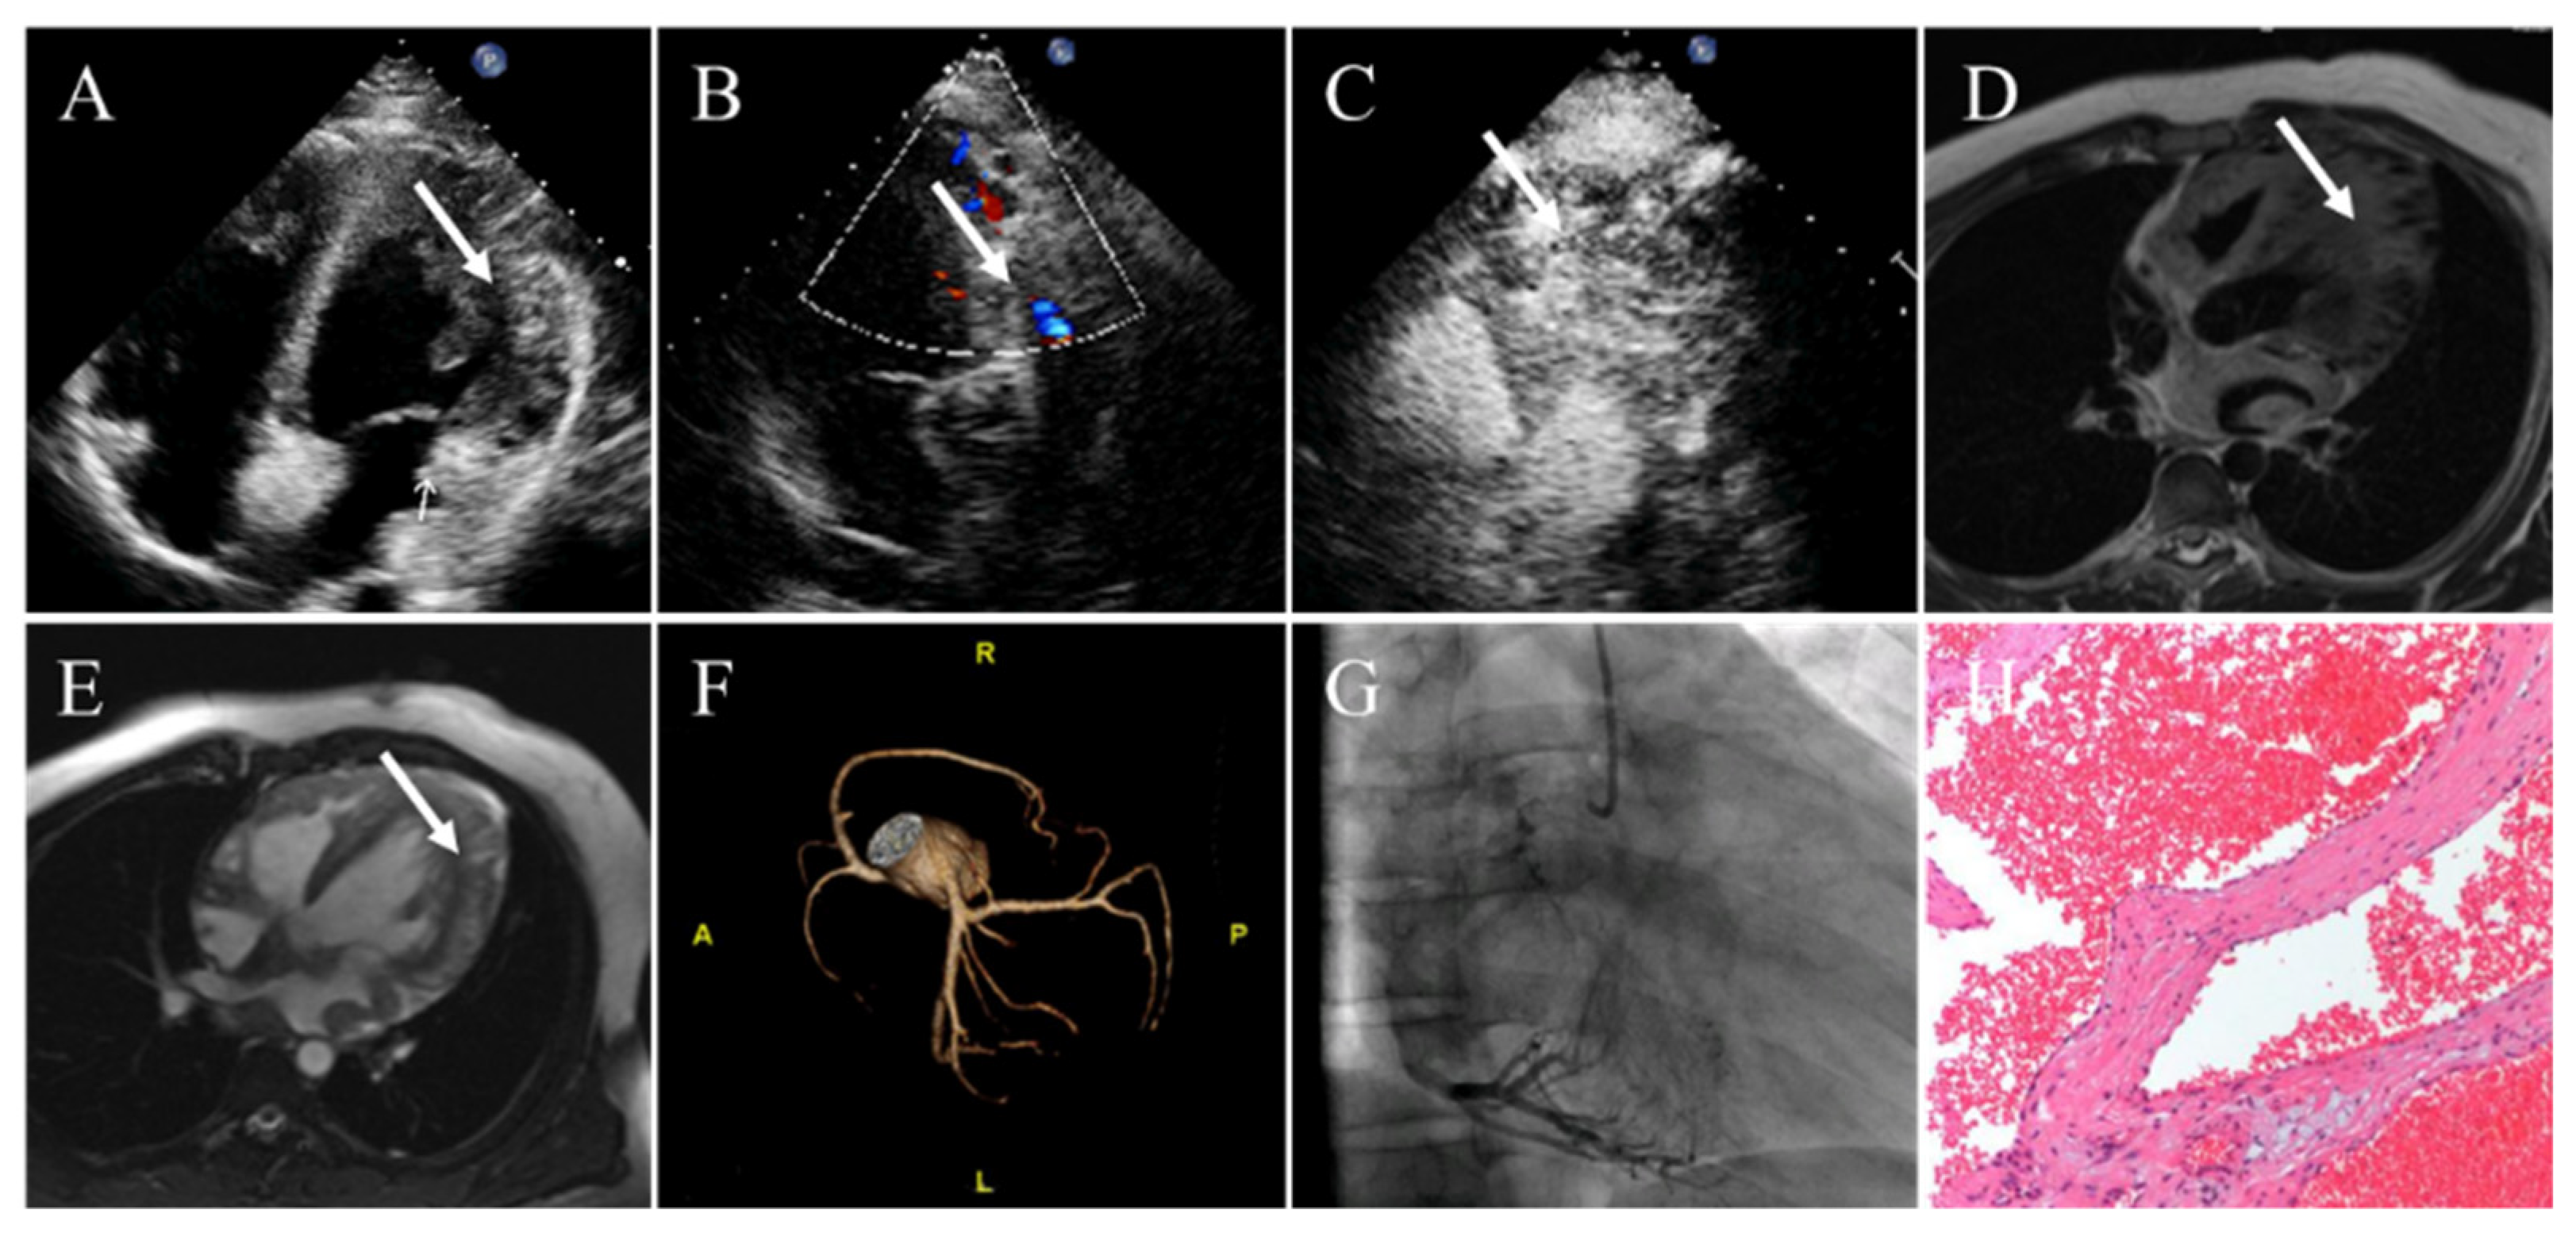

4.7. Hemangioma

| Hemangioma | Adulthood | Females | Ventricles | Well-circumscribed; oscillated with the cardiac cycle; blood flow signals on color Doppler flow imaging; obviously enhancement | Well-defined; low density or equal density; heterogeneous intense enhancement; “vascular blush” on coronary angiography | Heterogeneous isointense or hypointense on T1WI; hyperintense on T2WI; heterogeneous enhancement |

- Li, W.; Teng, P.; Xu, H.; Ma, L.; Ni, Y. Cardiac hemangioma: A comprehensive analysis of 200 cases. Ann. Thorac. Surg. 2015, 99, 2246–2252. [Google Scholar] [CrossRef]

- Miao, H.; Yang, W.; Zhou, M.; Zhu, Q.; Jiang, Z. Atrial hemangioma: A case report and review of the literature. Ann. Thorac. Cardiovasc. Surg. 2019, 25, 71–81. [Google Scholar] [CrossRef] [PubMed]

- Tourmousoglou, C.; Nikoloudakis, N.; Kelpis, T.; Tsotsolis, N.; Ninios, V.; Kallifatidis, A.; Ninios, E.; Theofilogiannakos, E.K.; Thoma, M.; Asimaki, A.; et al. Left ventricular cardiac hemangioma. Am. J. Med. 2017, 130, e337–e339. [Google Scholar] [CrossRef] [PubMed]

- Brizard, C.; Latremouille, C.; Jebara, V.A.; Acar, C.; Fabiani, J.N.; Deloche, A.; Carpentier, A.F. Cardiac hemangiomas. Ann. Thorac. Surg. 1993, 56, 390–394. [Google Scholar] [CrossRef]